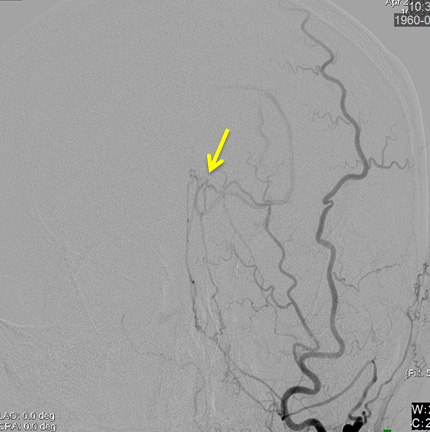

【DSA (左後頭動脈)】

後頭葉脳表に皮質静脈に直接灌流する動静脈瘻

• 側面

• 正面

診断:Cognard Type III 硬膜動静脈瘻による静脈性梗塞(静脈高血圧性脳症)